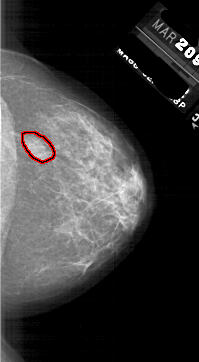

A_1764_1.RIGHT_CC

RIGHT_CC LINES 5791 PIXELS_PER_LINE 3181 BITS_PER_PIXEL 12 RESOLUTION 43.5 OVERLAY

FILE: A_1764_1.RIGHT_CC.OVERLAY

TOTAL_ABNORMALITIES 1

ABNORMALITY 1

LESION_TYPE MASS SHAPE OVAL MARGINS ILL_DEFINED

ASSESSMENT 4

SUBTLETY 4

PATHOLOGY BENIGN

TOTAL_OUTLINES 1

BOUNDARY